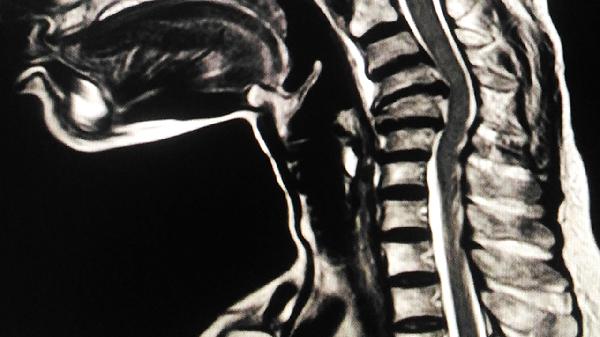

脊髓受压后脑部的指令还能下达吗

脊髓受压后脑部指令的下达能力取决于受压程度和部位,轻度受压可能仅导致部分信号传导障碍,重度完全受压则可能中断信号传递。主要影响因素包括受压位置、持续时间、是否伴随炎症水肿、基础神经功能状态以及是否及时干预。

颈椎段脊髓受压可能影响四肢活动,胸腰段受压则主要影响下肢功能。高位颈髓(C1-C4)受压最危险,可能直接阻断脑干与全身的神经连接,导致呼吸心跳中枢指令无法下达。不同节段脊髓包含的运动神经元和传导束分布不同,直接影响症状表现。

脊髓受压患者需保持每日1500-2000毫升饮水量预防泌尿系感染,采用定时翻身护理避免压疮。饮食应保证每日1.2-1.5克/公斤体重的优质蛋白摄入,补充B族维生素促进神经修复。康复期可进行被动关节活动度训练,配合经颅磁刺激等物理治疗。建议每3个月复查脊髓MRI评估神经恢复情况,出现肌张力异常增高或自主神经功能紊乱需及时就诊。